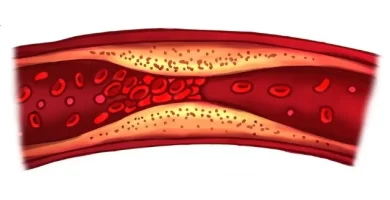

¿Cómo limpiar las arterias de forma natural?

Mantener las arterias sanas es crucial para prevenir enfermedades cardiovasculares, la principal causa de muerte en el mundo. La aterosclerosis, o la acumulación de placa en las arterias, es un proceso gradual que puede llevar a infartos y derrames cerebrales.